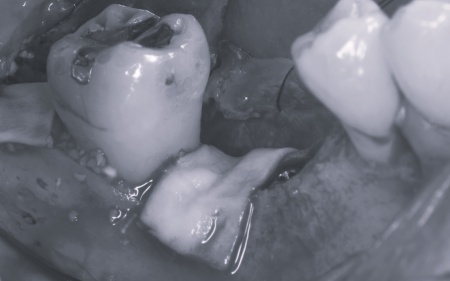

下左右の第1大臼歯を抜歯し、その部位にインプラントを埋め込む手術を行いました。同時に、インプラントの隣にある下の第2大臼歯に対して歯周組織再生療法を施しています。

さらにインプラントの周囲には角化歯肉移植を行いました。これは患者様のお口の中から歯ぐきを採取して移植する方法で、汚れが溜まりにくく清掃しやすい歯ぐきの状態をつくります。

上左右の奥歯についても歯周組織再生療法を行い、歯をできるだけ残せるよう治療を進めました。